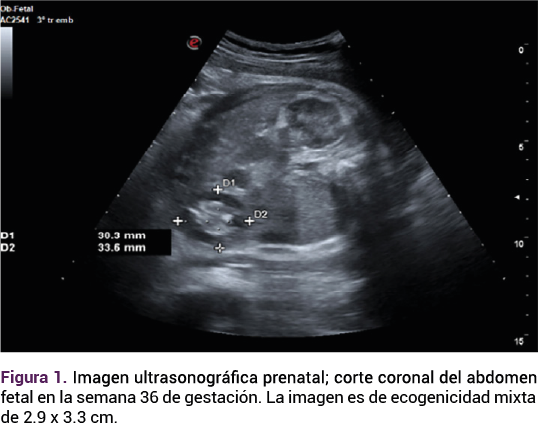

Durante su estancia en la unidad de cuidados neonatales se practicó una resonancia magnética que evidenció la tumoración, sin datos de infiltración a las estructuras adyacentes, que desplaza al intestino. Figura 4.

<strong>Figura 4</strong>

Figura 4.

La ecografía es el principal método diagnóstico para los teratomas testiculares, aunque su efectividad puede verse afectada por la variabilidad en la presentación clínica y la experiencia del operador, lo que puede llevar a un subdiagnóstico.4 En este caso resaltan varios puntos críticos, primero la importancia del seguimiento ecográfico detallado durante el embarazo, que puede facilitar intervenciones quirúrgicas oportunas y mejorar los desenlaces neonatales.6 De este caso puede interpretarse la necesidad del enfoque sistemático, con la incorporación de técnicas adicionales, como la resonancia magnética fetal, que se utiliza como técnica de imagen complementaria a la ecografía prenatal y ha sido validada en la investigación prenatal de las tumoraciones sólidas abdominales, anomalías del aparato gastrointestinal y genitourinario.7

En este caso la resonancia magnética se practicó en el periodo posnatal inmediato. Su protocolo debería incluir, siempre, secuencias potenciadas en T2, para la valoración de la anatomía, y también las potenciadas en T1.7 La resonancia magnética fetal no es de aplicación común para el tamizaje prenatal, aunque con el debido asesoramiento completo de la anatomía fetal su utilidad puede llegar a ser relevante.8 El diagnóstico prenatal puede ayudar en el asesoramiento y la planificación del parto en un entorno con acceso inmediato a la atención multidisciplinaria.8